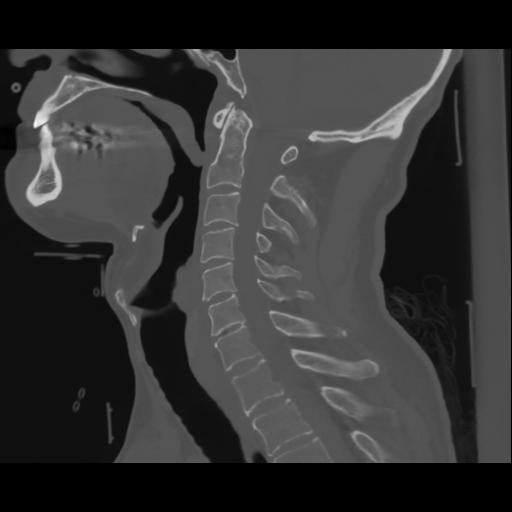

14 P.BLANDAS,,Sagittal,2.000,P.BLANDAS,Sagittal,